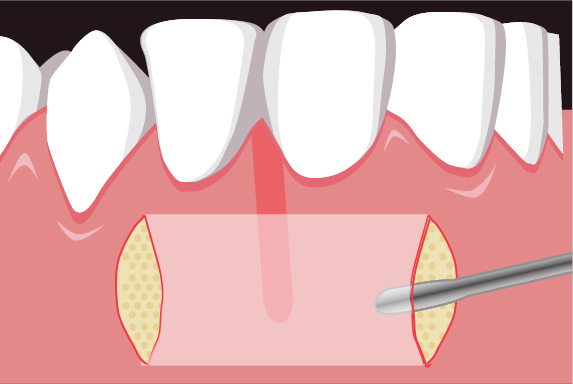

歯周組織再生療法は施術の難易度が高く、ほとんどの歯科では扱っていない内容です。

専門医資格を持つ医師が歯周組織再生治療を手がけるので、安心して治療を受けていただけます。